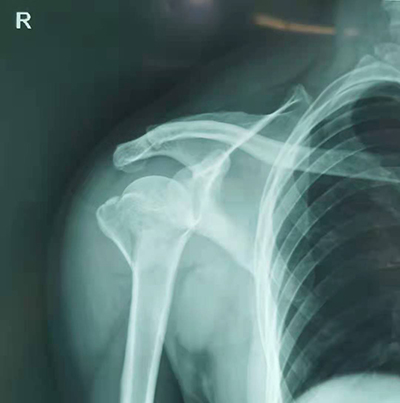

通過了解得知,46歲的敖先生騎電瓶車去上班的時候,不小心摔了一跤,右肩部立即感覺到腫痛,動彈不得。在好心路人的幫助下,撥通了120來到我院就診,我院并為敖先生開通綠色通道就醫,經查體后以“右肱骨近端骨折”收入住院。

骨科張廣院長得知后,快速制定手術治療方案,根據患者實際情況,定制了“右肱骨近端骨折切開復位內固定術+肩袖修補術”微創手術方案,并征得患者家屬同意。